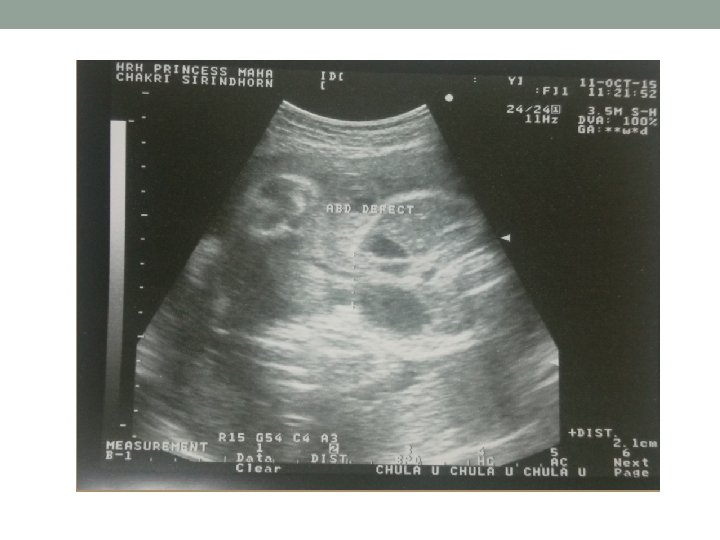

Transabdominal ultrasound(11/10/58) • Singleton fetus, intrauterine pregnancy • Cephalic presentation, EFW 1444 gm (<Percentile 5, reference จฬา ) • BPD 75. 5 mm/ 29+6 wk • HC 273 mm/ 29+4 wk • AC 251. 0 mm/ 29+2 wk • FL 55. 8 mm/ 29+3 wk • Fetal movement: positive, fetal cardiac activity: positive • AFI: 14. 2 cm

Transabdominal ultrasound(11/10/58) • Placenta: posterior middle, grade II, no placenta previa • No venticulomegaly • No cleft lips • Four cardiac chamber, not clearly seen LVOT, RVOT due to fetal position • Abdominal wall defect 2 cm, no liver protrude suspected gastroschisis • Seen both kidney, bladder